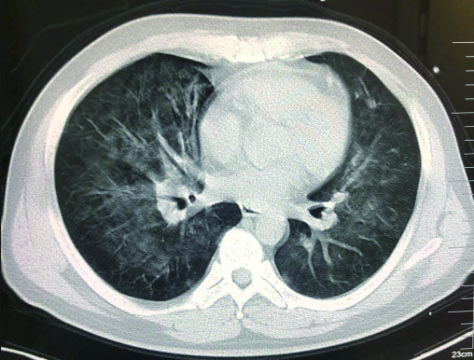

1.2 临床表现和检查患者初期有咳嗽症状,但未在意,患者回家24 h后咳嗽症状加重,伴胸闷气喘,全身大汗淋漓,家属立即将其送至本院急诊,为进一步诊治拟“有机氟中毒”收住入院。入院时体检:神志清楚,T:36.5℃,R: 57次/min,BP: 146/71 mmHg,胸廓对称无畸形,呼吸急促,听诊双肺呼吸音清晰,可闻及大量湿性啰音,心率112次/min,心律齐,心音正常,各瓣膜听诊区未闻及病理性杂音及心包摩擦音,四肢关节正常,双下肢无水肿,深浅生理反射正常,病理反射阴性,脑膜刺激征阴性。辅助检查:白细胞计数10.45×109/L,中性粒细胞91.9%;C-反应蛋白14.81 mg/L, 无创机械通气支持下血气分析pH7.28,PCO2 50 mmHg, PO2 57 mmHg, Lac 3.0 mmol/L(FiO2 50%),为Ⅱ型呼吸衰竭,给予无创呼吸机辅助呼吸、激素冲击、解痉平喘等抢救治疗。急诊胸部CT检查提示:两肺散在斑片状模糊影,密度不均,边界不清(图 1),进ICU床边胸片提示:两肺散在斑片状模糊影(图 2)。根据GBZ5—2016《职业性氟及其无机化合物中毒的诊断》的诊断标准,该患者诊断为职业性急性重度有机氟中毒。

| 图 1 3月10日胸部CT |